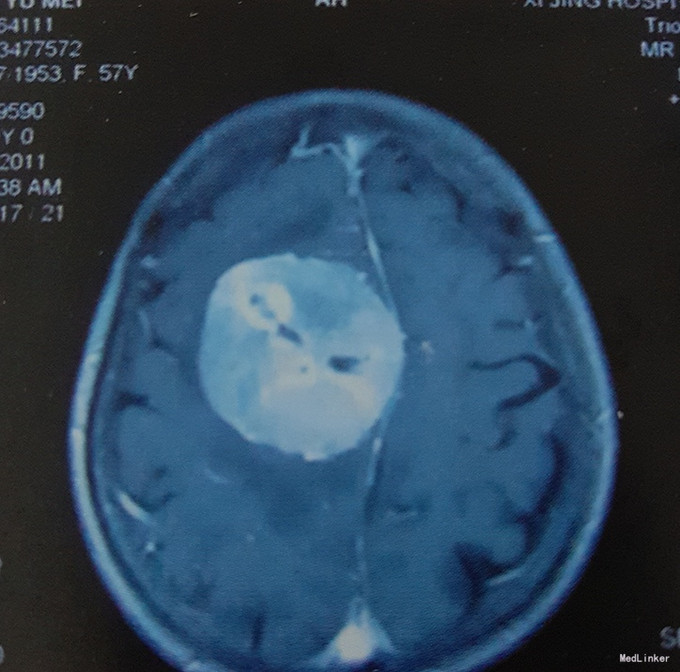

患者女,57岁,主因”头痛、头晕伴左侧肢体无力半月“入院。 患者于入院前半个月无明显诱因出现头痛、头晕,伴左侧肢体无力,行走时步态不稳,遂至当地医院就诊。无癫痫病史,无其他特殊不适,既往无特殊病史。

查体:心肺腹体检无明显异常,生命体征平稳,左上肢及左下肢肌力IV级,右侧肢体肌力V级,四肢肌张力正常,其他神经系统检查无明显异常。 颅脑MRI增强扫描:右顶部中央沟区矢状窦-镰旁巨大占位,强化效应明显,质地均匀边界清,中线及周围脑组织明显受压。

诊断:右顶中央沟区矢状窦-镰旁巨大占位。 治疗:入院后在全麻下行开颅探查右顶中央沟区矢状窦-镰旁巨大脑膜瘤切除术。 术后病理结果回报示:右顶矢状窦旁-镰旁纤维型脑膜瘤(WHO I级)。